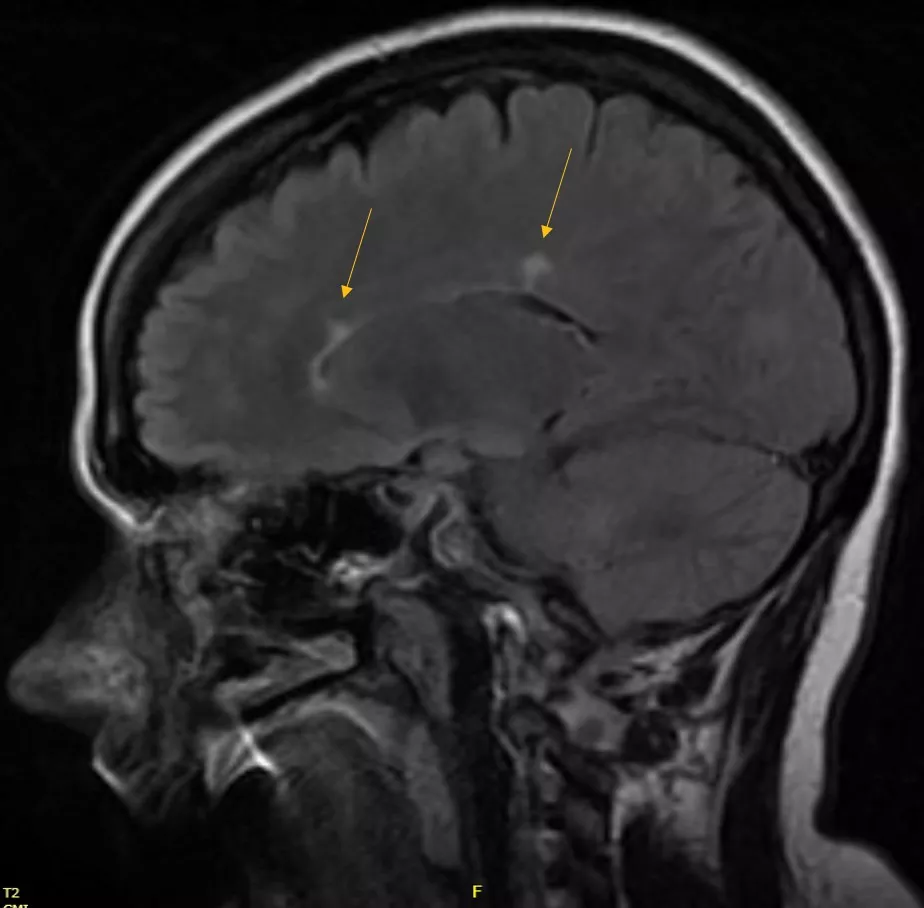

2021 Brain MRI

She had an actively enhancing juxtacortical lesion present in the left temporal region.

Mizell - MS 3-6